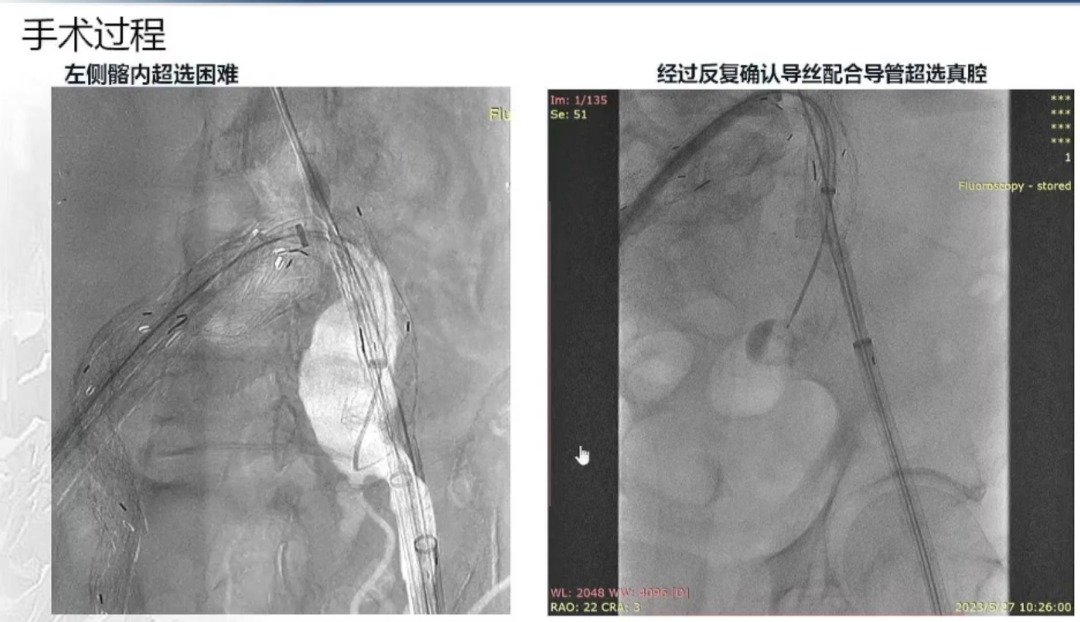

左侧髂内动脉超选与重建

右侧髂内动脉重建完成后,建立对侧翻山通路,再次确认主体位置及左侧髂内动脉情况。左侧髂内超选困难,经反复确认导丝配合导管超选真腔,手推造影确认髂内情况后释放远端VB,释放左侧髂内分支HGB并确认通畅情况。最后按常规EVAR置入腹主动脉支架主体,超选入主体短腿内对接IBE主体释放桥接喇叭腿。

左侧髂内分支HGB释放

手推造影确认通畅情况